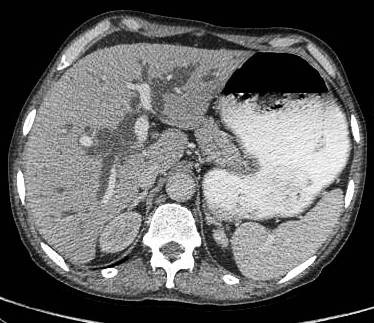

Common patterns of carcinoma gallbladder

Three patterns have been described on ultrasonography (US). The gallbladder fossa is replaced by a heterogeneous mass (figure 1) with internal areas of necrosis; or there may be diffuse, irregular, and asymmetrical wall thickening (Figure 2); or less commonly, a polypoidal, fungating intra-luminal mass is seen. Correct preoperative diagnosis has improved considerably with the use of newer imaging techniques [6-8]. Majority of cases when diagnosed, are no longer resectable (Figure 3) [9-11].

Figure 1: large gallbladder fossa mass replacing the entire gall bladder. Discrete liver secondaries can be seen.

Figure 1: Large gallbladder fossa mass replacing the entire gallbladder. Discrete liver secondaries can be seen.